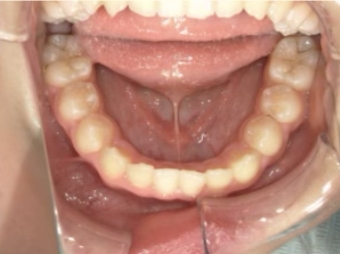

治療中⑤ 小5:10y11m

モノブロック装置継続中、左上3が八重歯で萌出